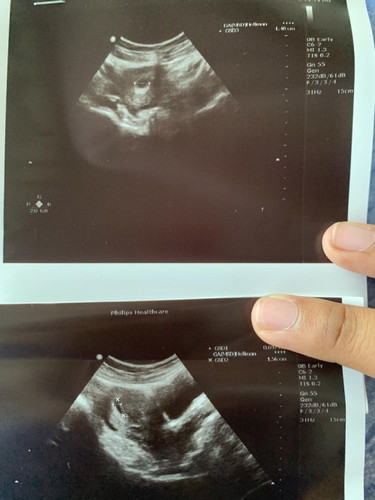

ผลอัลตร้าซาวด์

หลังจากตรวจว่าตั้งครรภ์ วันที่ 15 ได้ทำงานไปฝากครรภ์หมอซาวให้ยังไม่เจออะไรเลยทั้งถุงละตัวอ่อน แล้วนัดอีกทีวันที่ 26 คือวันนี้คะ วันนี้ผลออกคือพบถุงตั้งครรภ์แล้ว แต่ยังไม่เห็นตัวน้องคะ หมอนัดซาวอีก 2 สัปดาห์ กังวลมากคะ แม่ๆ ท่านไหนเคยเป็นแบบนี้บ้างคะ